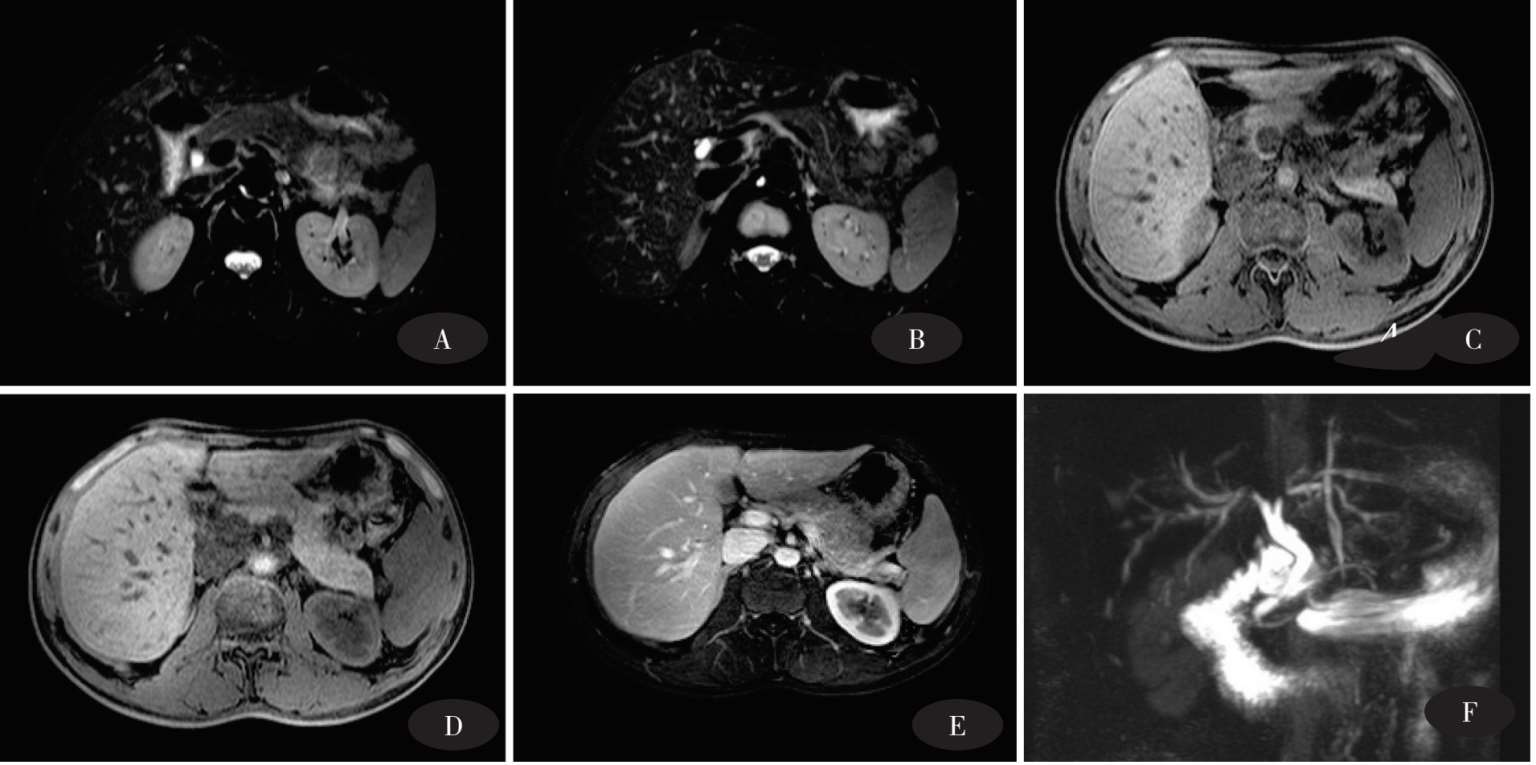

图8-5 胰头癌MRI平扫+增强+DWI+MRCP+MRA

图8-5A FSE-T2WI-FS:病灶呈不均匀高信号改变,边界不清。图8-5B FLASH-T1WI-FS:病灶呈不均匀低信号改变,胰管扩张呈低信号。图8-5C FLASH-T1WI-FS+C:病灶呈不均匀轻度强化。图8-5D、图8-5E DWI:病灶呈明显弥散受限,边界不清。图8-5F MRCP:肝内胆管及肝外胆管明显扩张,呈“软藤征”改变。胰管扩张,与扩张胆总管呈“双管征”改变;图8-5G、图8-5H MRA:门脉明确受侵、缩窄。